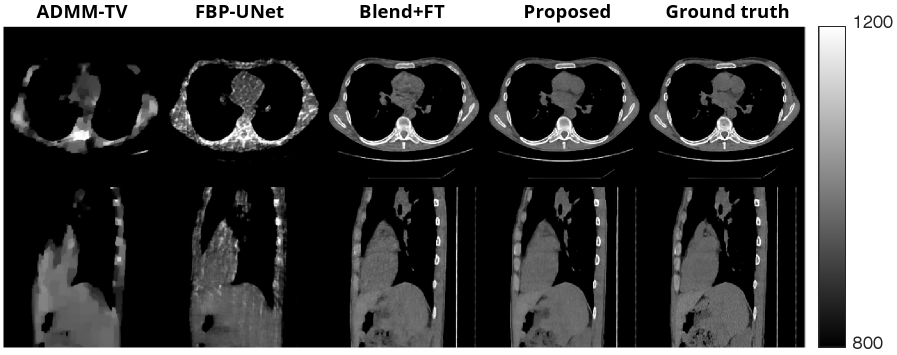

We conduct experiments of sparse-view CT (SVCT) reconstruction from 8, 20, and 60 views on one of the test volumes. The results in Table 1 and Figure 4 demonstrate that our method is able to reconstruct high-quality images. Furthermore, we compared our proposed method with various classical methods and diffusion model methods for 3D CT reconstruction. We used the filtered back projection method with a ramp filter, whose implementation is found in [chung:22:s3i]. We also used the total variation (TV) regularizer and solved the optimization problem using ADMM (ADMM-TV) with the implementation in [Hong_2024]. For the other baseline, we implemented FBP-UNet [fbpconvnet] which is a supervised method that involves training a UNet that maps FBP reconstruction to the clean image. Since FBP-UNet is a 2D method, we learned a mapping between 2D slices and then stacked the 2D slices to get the final 3D volume.

For diffusion model methods, we ran DDS [chung2024decomposeddiffusionsampleraccelerating] and DiffusionBlend [song2024diffusionblendlearning3dimage]. To obtain the best possible results for DiffusionBlend, we used the trick in the original work that involved taking a network that was pretrained on ImageNet and then finetuning it on the relevant CT dataset. Thus, we specifically ran DiffusionBlend++ with the prior trained on groups of 3 slices. To illustrate the effect of using the pretrained network, we show experiments both with the finetuning method (Blend+FT) and with networks that were trained from scratch on the CT datasets. Since our proposed method does not rely on a pretrained network, the most fair comparison is with [song2024diffusionblendlearning3dimage] without a pretrained network; nevertheless we showed both results to illustrate how our proposed method can obtain superior results. Both of these methods were run with 200 sampling steps. The appendix provides the experiment parameters.

Refer to caption

Figure 4: Results of our proposed method and comparison methods for 20 view CT recon on LIDC 256×256×256256\times 256\times 256 dataset. Images are shown in modified Hounsfield units. The top row shows the axial slice and the bottom row shows the sagittal slice from the reconstructed volume.